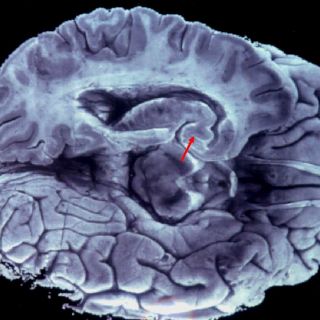

Esta pérdida de tejido cerebral se refleja en el grado de discapacidad del paciente, ya sea motora o cognitiva. Gracias a la incorporación de la resonancia magnética a los estudios de imagen que se hacen a los pacientes con enfermedades neurológicas como la esclerosis múltiple, el Alzheimer o el Mal de Parkinson, se ha podido identificar las lesiones clásicas de estos padecimientos.

La volumetría se basa en las imágenes de resonancia magnética que permiten hacer un contraste entre la sustancia gris y la blanca, mediante ciertos algoritmos que determinan el volumen de cada una de ellas, además es posible calcular la atrofia cerebral.